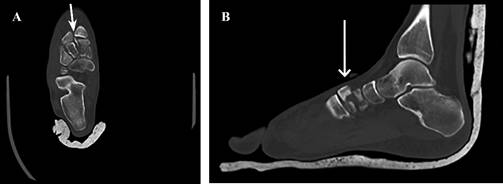

Lesiones por aplastamiento del mediopié, la presencia de patrones de fractura con conminución y acortamiento, comprometen la estabilidad de la columna media del pie. En estas situaciones, la utilización de fijador externo y/o agujas de Kirschner puede no proporcionar suficiente rigidez para sostener la reducción sobre el tiempo. La fijación con placa puente es la opción para lograr mantener la fijación en forma más estable, hasta que la consolidación sea alcanzada. Esta placa se extiende desde el primer metatarsiano al escafoides tarsiano o incluso al cuello del talo, si el escafoides presenta gran conminución que precluya la fijación en este lugar.49 En este último caso, el retiro de la placa después de cuatro a nueve meses debe hacerse para restaurar la función en el arco transverso y en la articulación subtalar, dado el efecto deletéreo que genera el bloqueo de la articulación escafoastragalina sobre la articulación calcáneo cuboidea y subtalar (Figura 4).50